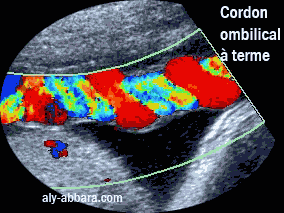

Image échographique montrant l'aspect du cordon ombilical à terme ( 41 SA)

On constate sur cette image la pulsativité des deux artères ombilicales avec une

veine ombilicale unique non pulsative.

Le cordon ombilcal à terme : les deux artères et la veine